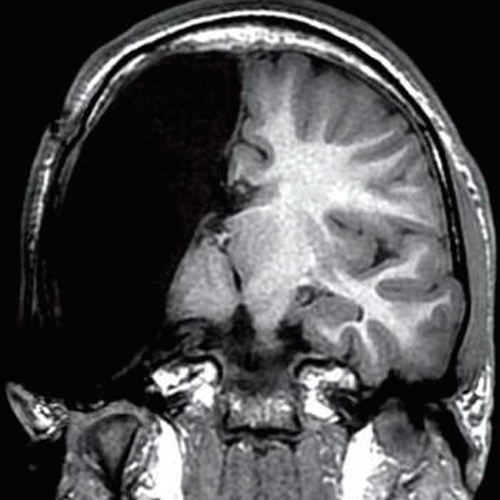

• Callosotomía (anterior, posterior, completa):

• Es un procedimiento paliativo de desconexión entre ambos hemisferios cerebrales, puede mejorar el control de las crisis epilépticas. Está indicado principalmente en crisis atónicas o las llamadas drop attacks / head drops.